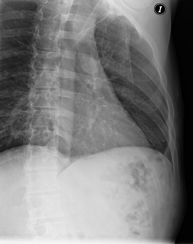

- RX Columna dorsal

Técnica mediante la cual, utilizando rayos X, se obtienen imágenes de la columna dorsal para su estudio. Indicaciones: traumatismo, dolor, escoliosis.

Técnica mediante la cual, utilizando rayos X, se obtienen imágenes de la columna dorsal para su estudio. Indicaciones: traumatismo, dolor de espalda.

- RX Columna lumbar

Técnica mediante la cual, utilizando rayos X, se obtienen imágenes de la columna lumbar para su estudio. Indicaciones: ciática, traumatismo, dolor lumbar.